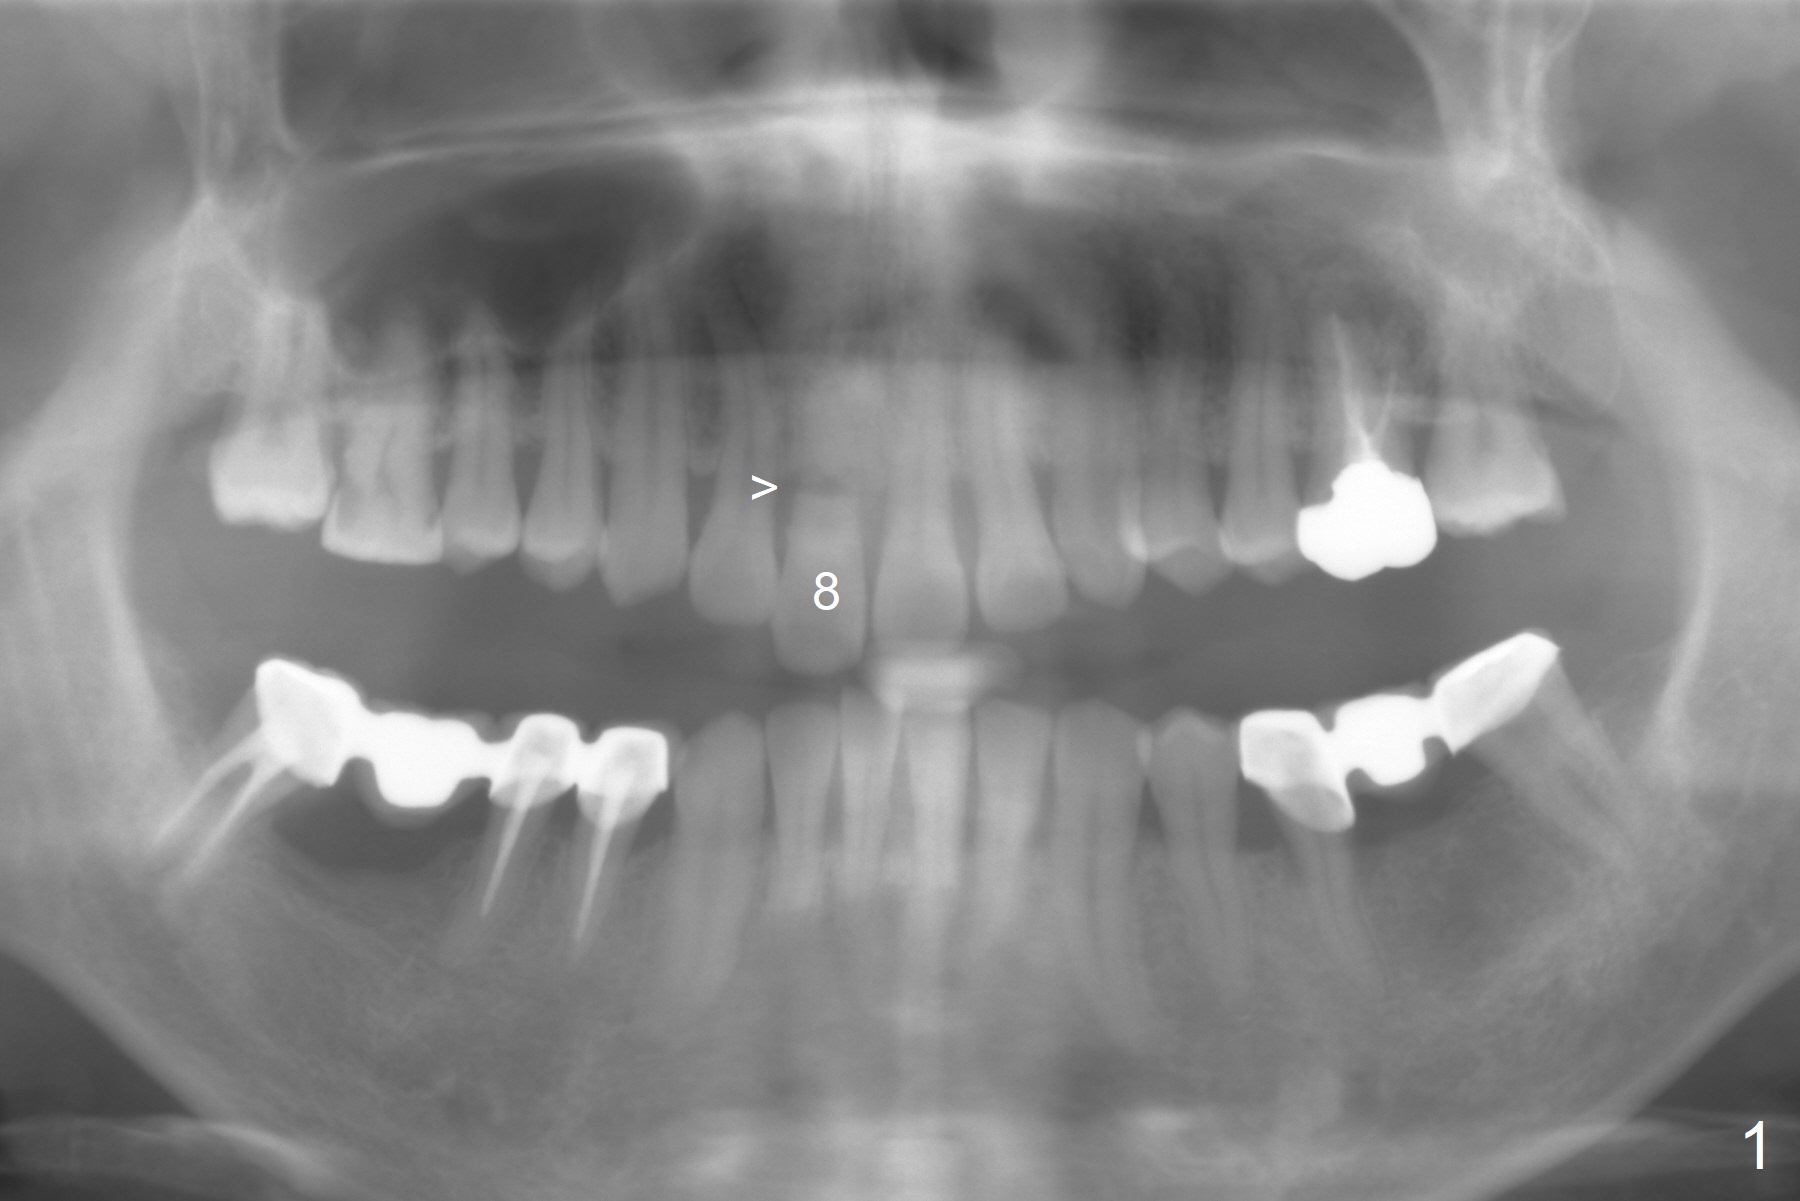

A 37-year-old man has fractured the root of the tooth #8 for a year (Fig.1). It appears that the longest bone-level implant is indicated (Fig.2). Take preop photos and PA if it is symptomatic with fistula.